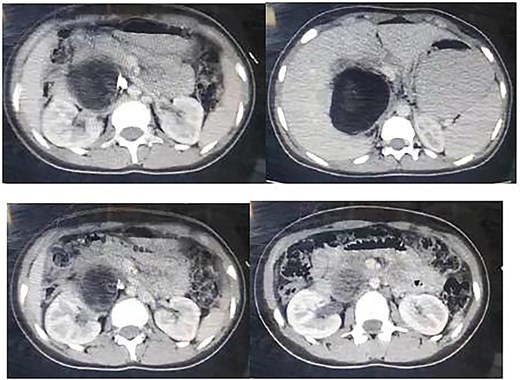

Ultrasound revealed a large lesion in the caudate lobe of the liver with a hypoechoic, cystic structure and a thin wall, suggestive of an atypical type IV hydatid cyst. The lesion showed well-defined margins and scattered calcifications within the wall. A non-contrast computed tomography (CT) scan confirmed a large hypodense cyst in the caudate lobe extending to the hepatic hilum, measuring 7.7 × 9.5 cm, with calcified wall components (Fig. 1). No intrahepatic biliary dilation or lesions in other organs were observed.

Non contrast CT showing a large hypogenous cyst of the caudate liver lobe lengthen to the hepatic hilum, dimensions of 7.7 × 9.5 cm with calcified composition of the wall.